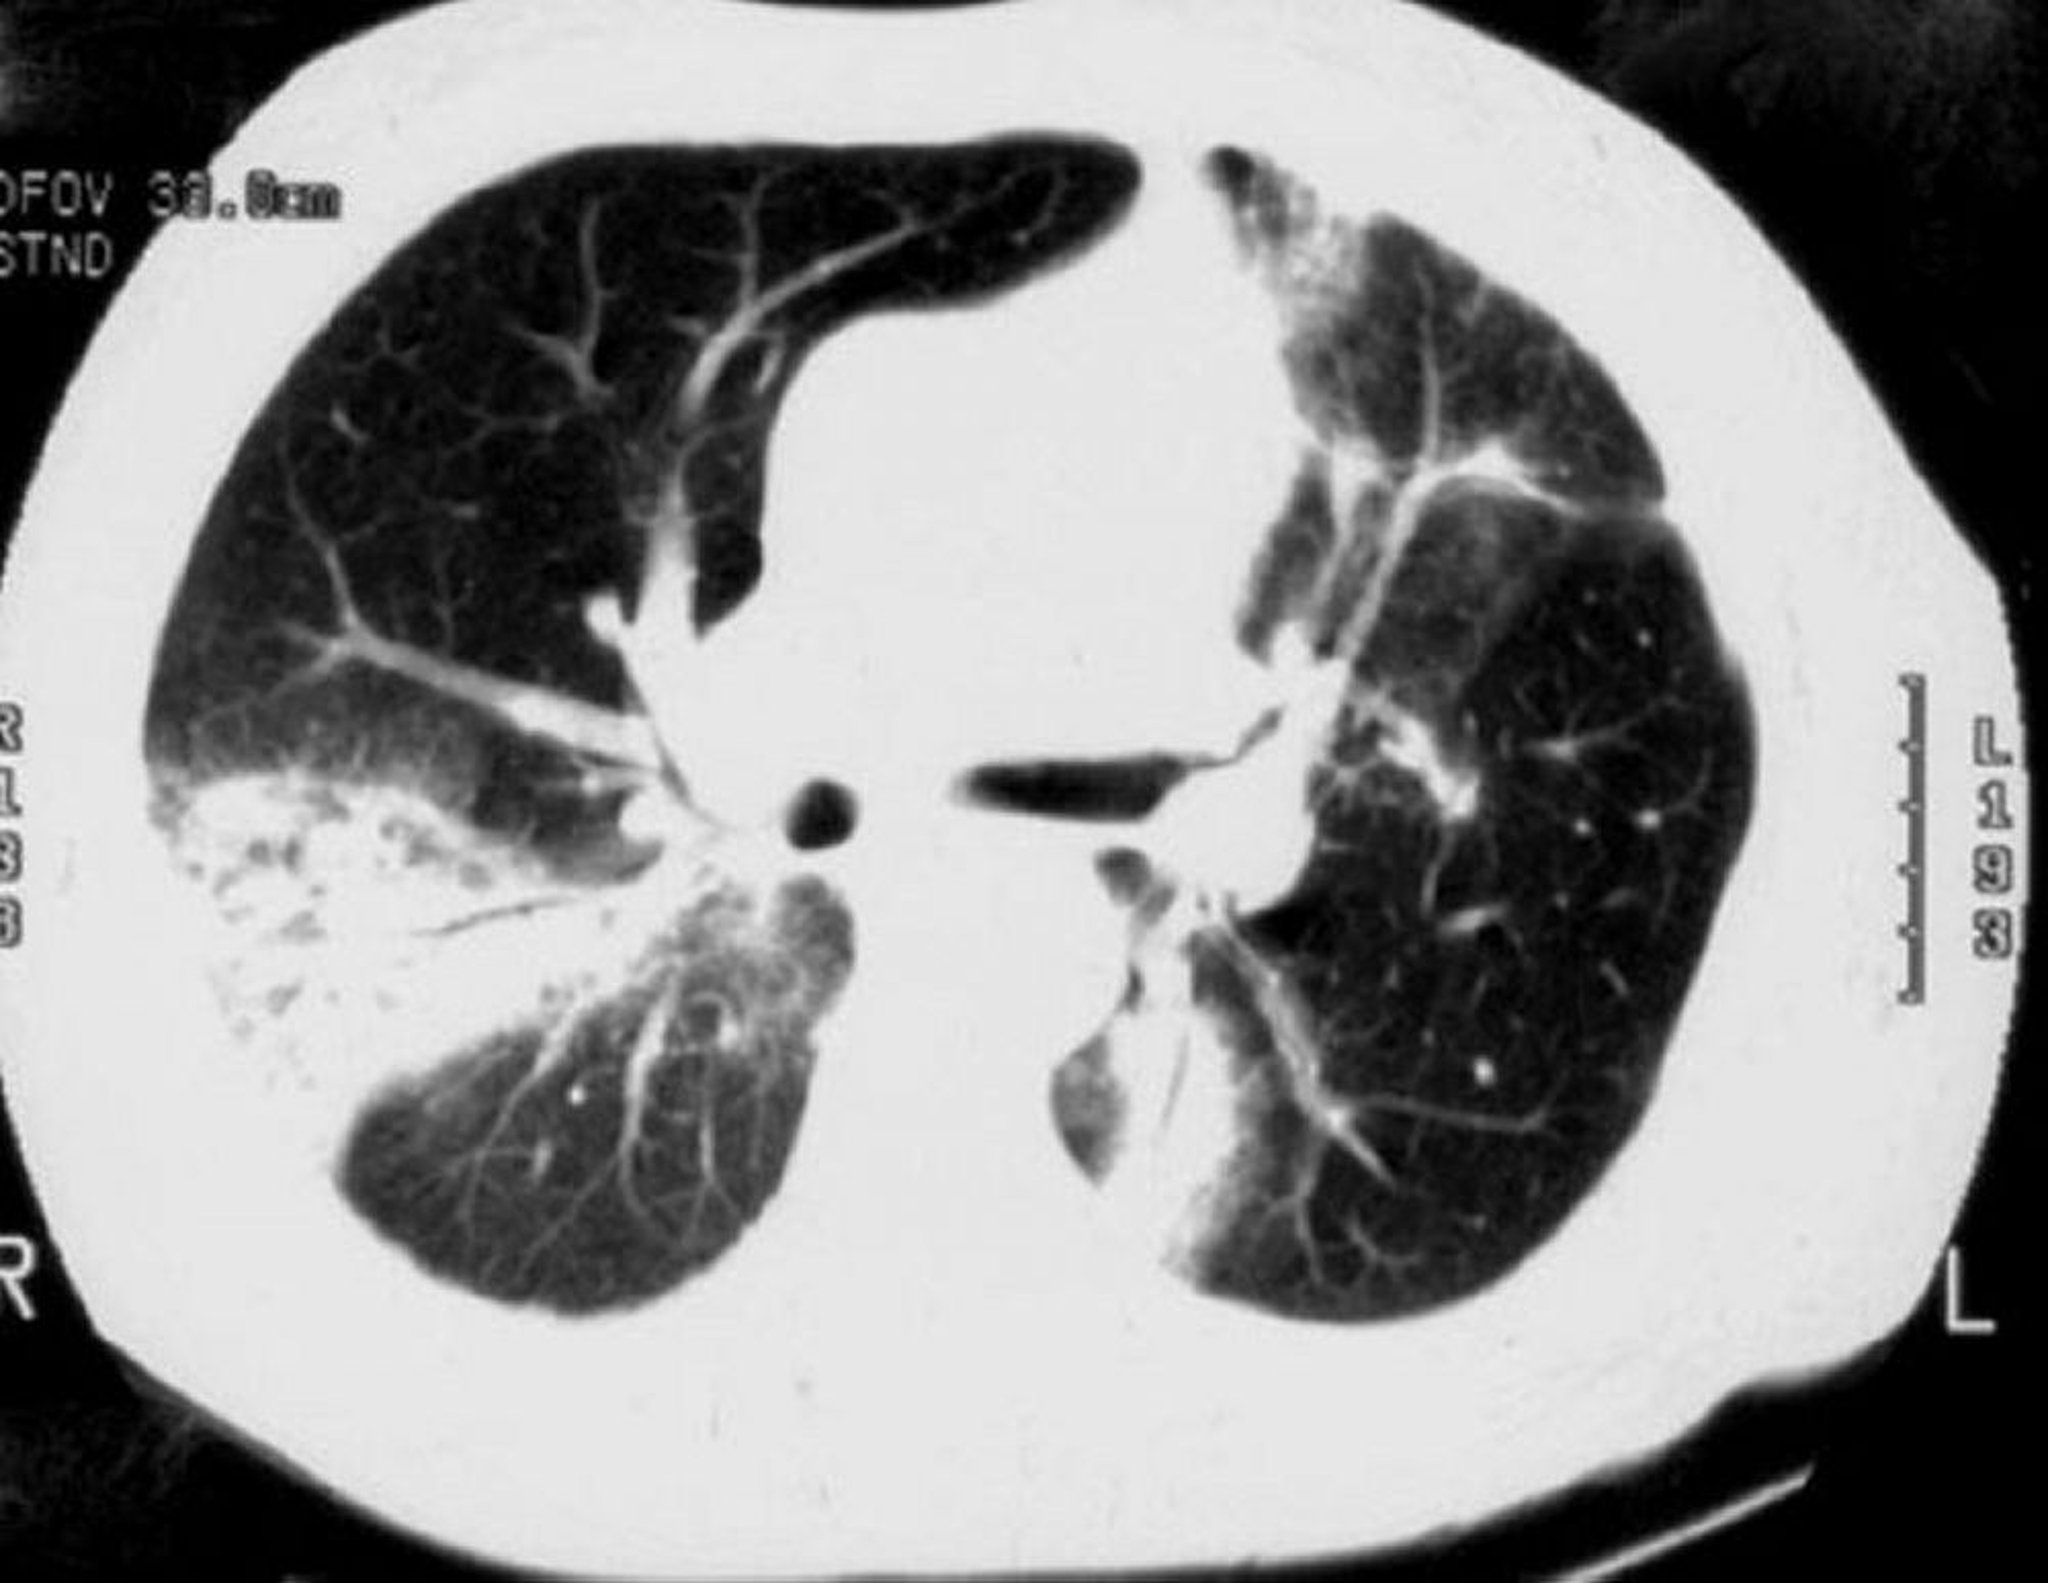

Neumonía organizada criptogénica

La tomografía computarizada de alta resolución muestra consolidación en parches de espacios aéreos, opacidades en vidrio esmerilado, opacidades nodulares pequeñas y engrosamiento de la pared bronquial con dilatación de la luz (broncograma aéreo).

Image courtesy of Talmadge E. King, MD.